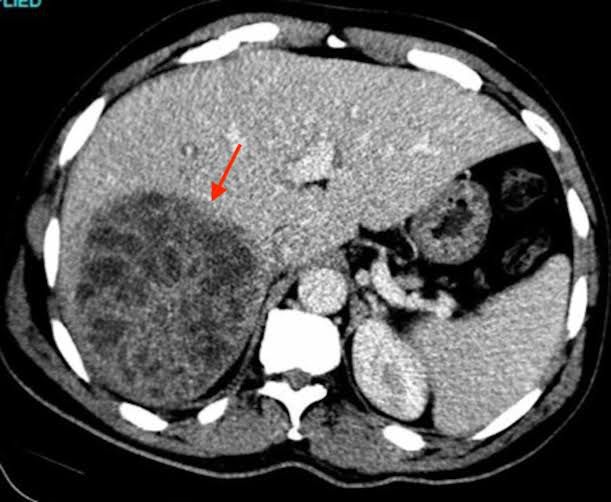

A liver abscess is defined as a pus-filled mass in the liver that can develop from injury to the liver or from an intra-abdominal infection disseminated from the portal vein. The majority of these abscesses are categorized as pyogenic or amoebic, although a minority are caused by parasites and fungi.